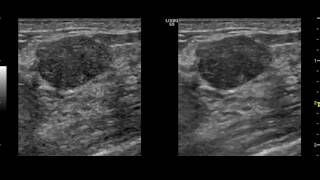

Плоскоклеточный рак бду может возникнуть в различных органах, включая легкие, голову и шею, кожу, пищеварительную систему и другие. Поэтому, точный подход к лечению будет определяться конкретной локализацией опухоли и ее масштабом.